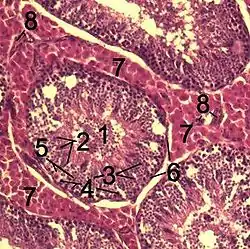

Histological section through testicular parenchyma of a boar. 1 Lumen of convoluted part of the seminiferous tubules, 2 spermatids, 3 spermatocytes, 4 spermatogonia, 5 Sertoli cell, 6 myofibroblasts, 7 Leydig cells, 8 capillaries | |